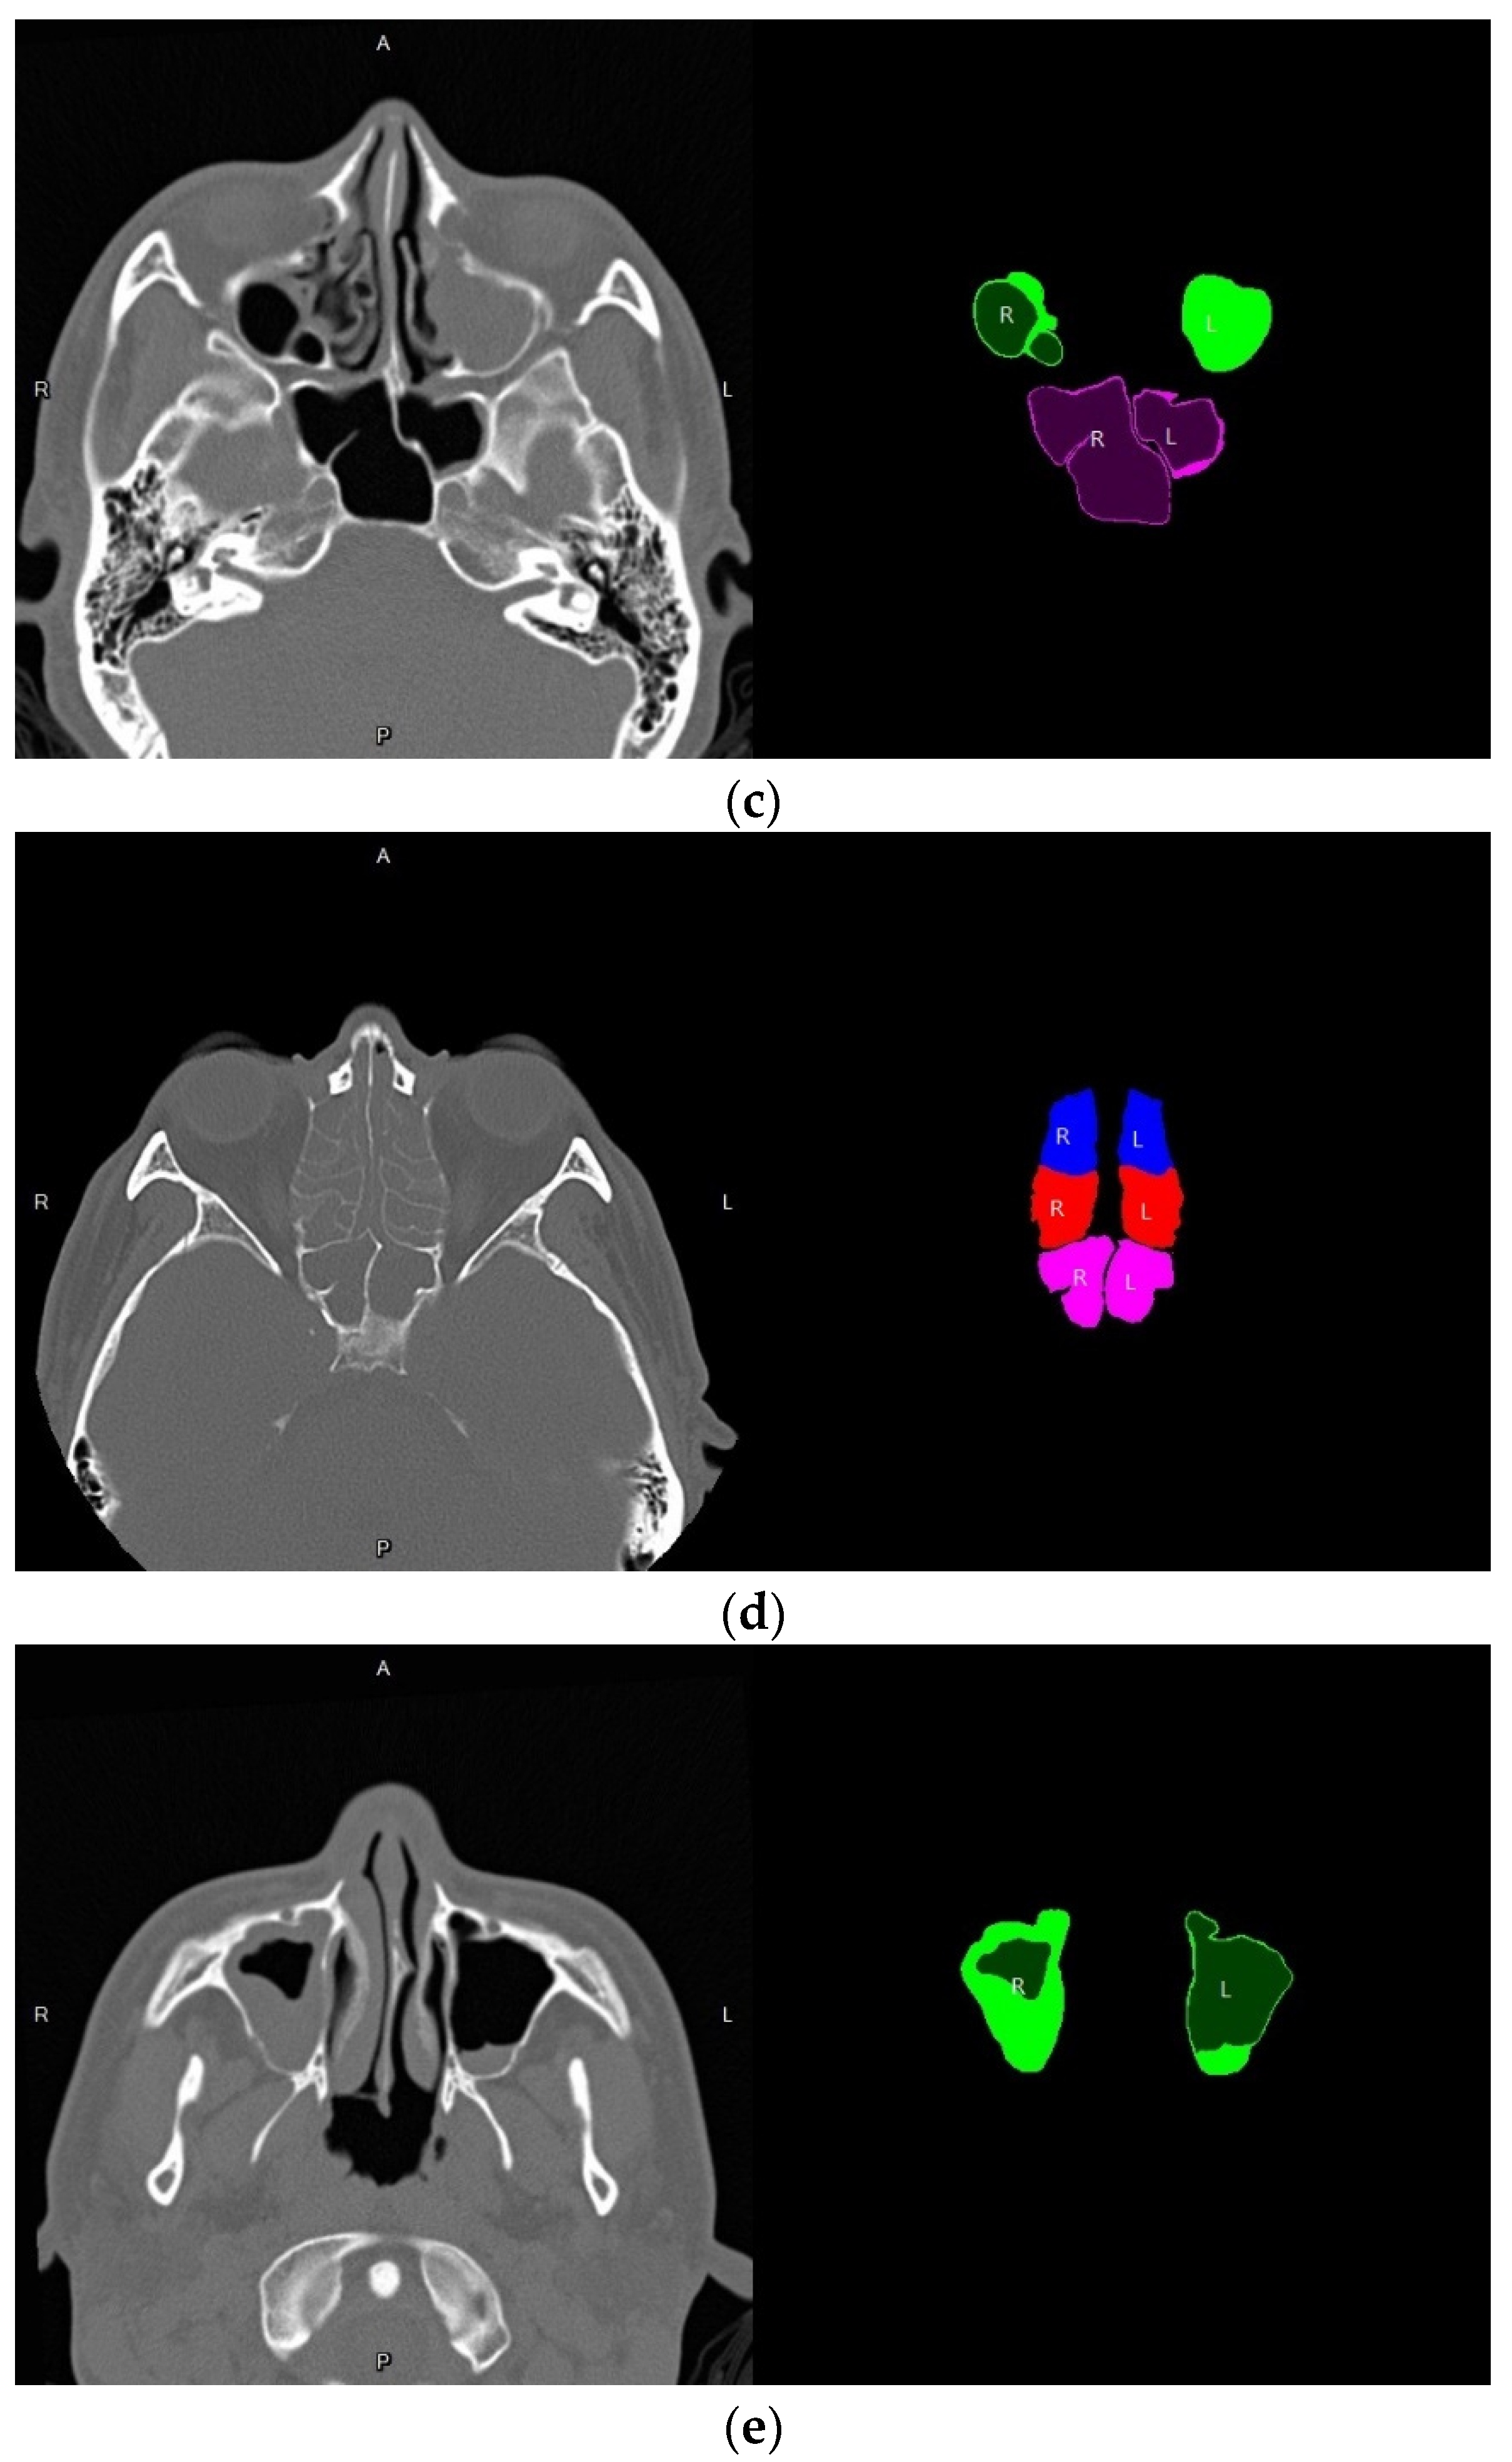

3.4. Volume Reconstruction

3.4.1. Morphology

3.4.2. 3D Reconstruction